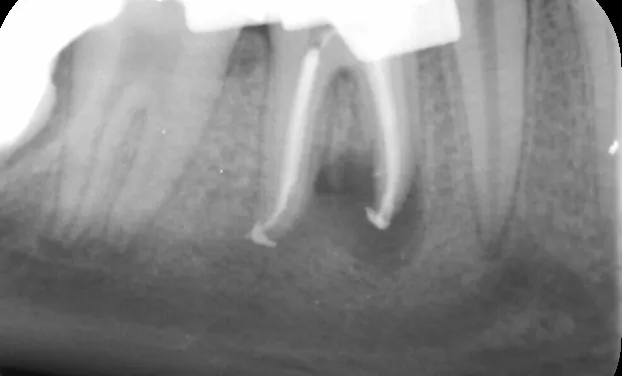

The Endodontic treatments in our clinic are done by Dr Maria Moukarzel.

Endodontics is the study, prevention, diagnosis, and treatment of diseases associated with the roots of the teeth. Endodontic services aim to save the patient’s natural teeth by restoring dental health and function.